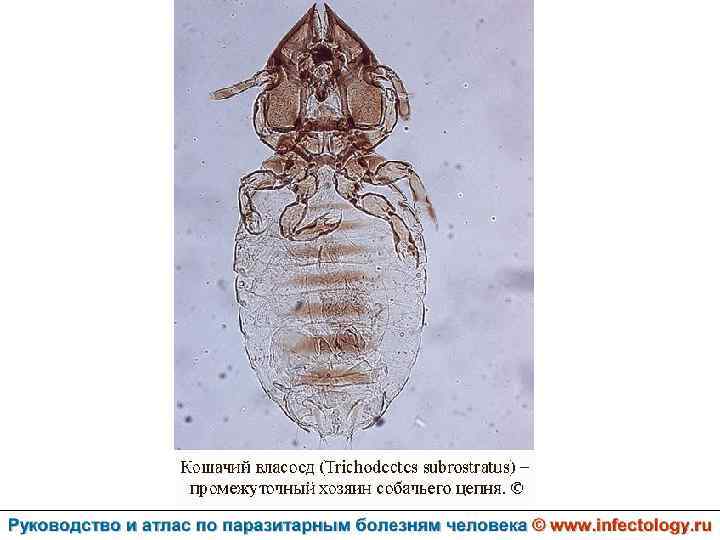

Дипилидиоз (шифр по МКБ 10 – B 71. 1) зоонозный биогельминтоз, характеризующийся аллергизацией организма и нарушением функций пищеварительного тракта.